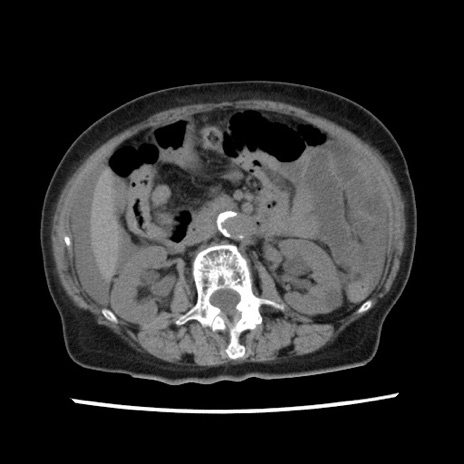

症例1(横断像)

【症例】80歳代女性

【主訴】腹痛

【現病歴】8時間前から腹痛あり来院。

【既往歴】糖尿病、脂質異常症、子宮体癌にて子宮全摘術

【身体所見】意識清明・会話良好だが腹痛で苦悶様、全腹部にわたって反跳痛と圧痛あり

【データ】WBC 13600、CRP 0.14、LDH 224、CK 90